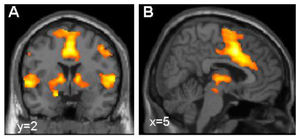

Aktivierung des "Furchtnetzes" im Gehirn (Foto: Tina Lonsdorf, UKE Hamburg) |

Es sind aber wieder andere Varianten des Gens GLRB, die nun erstmals mit Angst- und Panikstörungen in Verbindung gebracht werden. Sie treten häufiger auf und haben vermutlich nicht so schwere Auswirkungen. Aber auch sie führen zu überschießenden Schreckreaktionen und in der Folge möglicherweise zu einer übermäßigen Aktivierung des "Furchtnetzwerkes" im Gehirn. Das schließen die Würzburger Forscher aus hochauflösenden Bildern, die sie von den Gehirnaktivitäten der Studienteilnehmer gemacht haben.